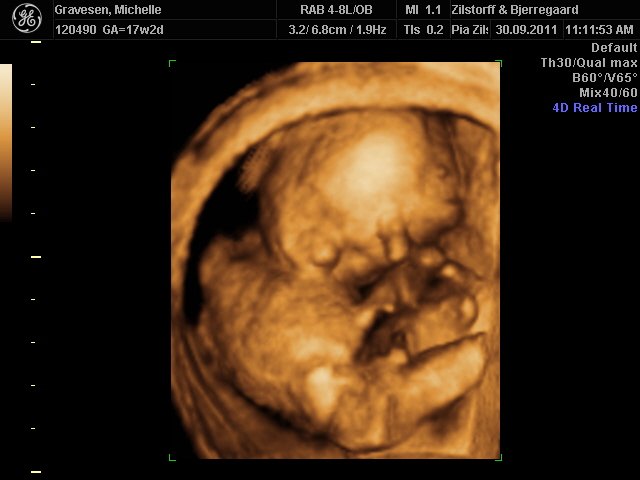

Så fik vi langt om længe klar besked på hvilket køn min kæreste har i maven

Og som flertallet af jer der deltog i billedafstemningen sagde var det det en dreng.

Så vi glæder os begge rigtig meget til at få vores lille supermand til verden